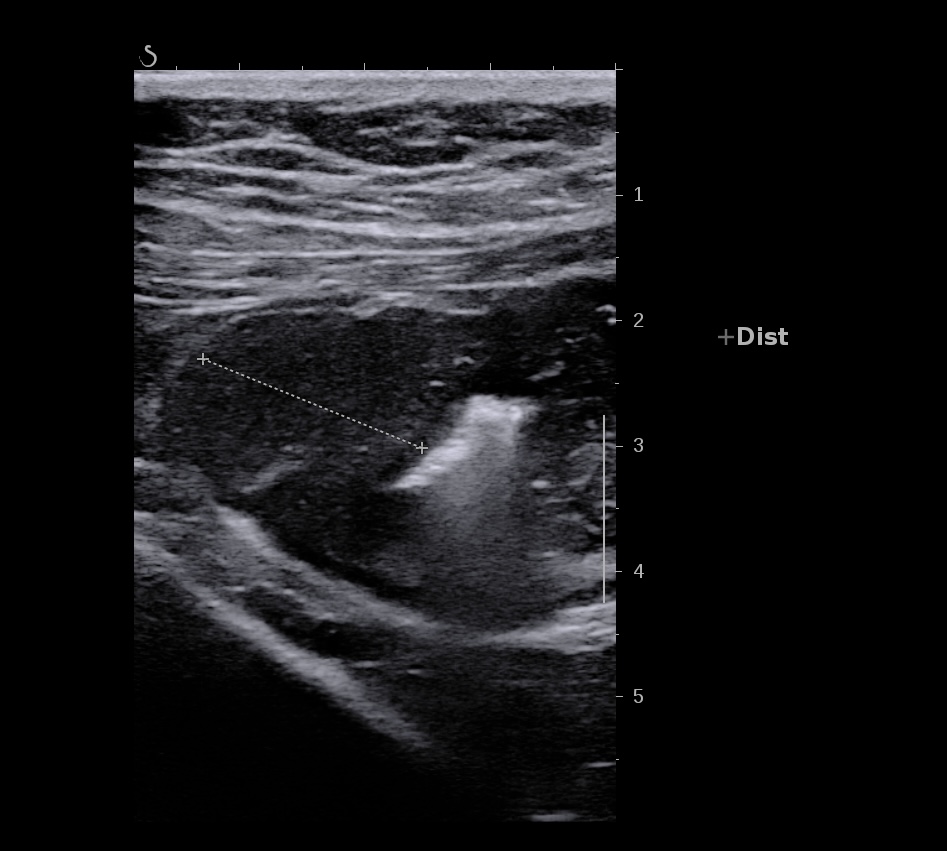

Epaississement entre 4.5 et 7 mm selon les segment, la structure en couche disparait totalement par endroit, à d’autre elle est partiellement conservée. Activité doppler intense de la paroi

Le Score de Milan (MUC) est à (1,4 x7+2) = 11,8

Echographie: pancolite jusqu’à l’angle droit, Paroi 7 mm perte de la stratification, doppler positif.